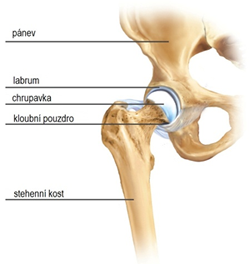

Anatomie

Kyčelní kloub je kulovitý kloub, ve kterém artikuluje pánevní jamka (acetabulum) a hlavice kosti stehenní. Styčné plochy těchto kostí jsou kryty hyalinní chrupavkou. Plochu jamky formuje její kostěná část, na jejíž okraj nasedá chrupavčité labrum. Kyčelní kloub je staticky stabilizován silným kloubním pouzdrem a dynamicky svalovým pláštěm. Důležitými svaly při stání a dopředném pohybu jsou zejména gluteální svaly, iliopsoas a hamstringy. Po přední a zadní straně kloubu probíhají důležité nervy. Po přední ploše kyčelního kloubu probíhají cévy zásobující celou dolní končetinu.